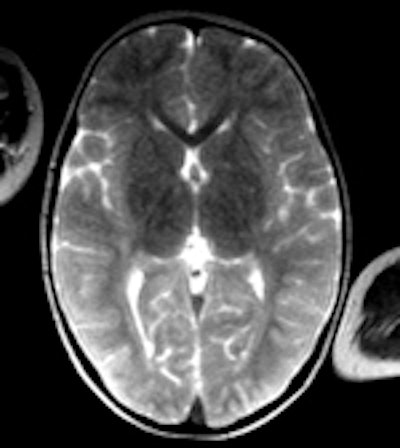

In an earlier work with the Institute of Forensic Medicine at the University of Bern, published in 2008, Grabherr showed how retrograde perfusion of the venous system visualized vascular abnormalities that helped confirm suspicions that the causes of death were drug intoxication (American Journal of Roentgenology, February 2008, Vol. 190:2, pp. 345-351).